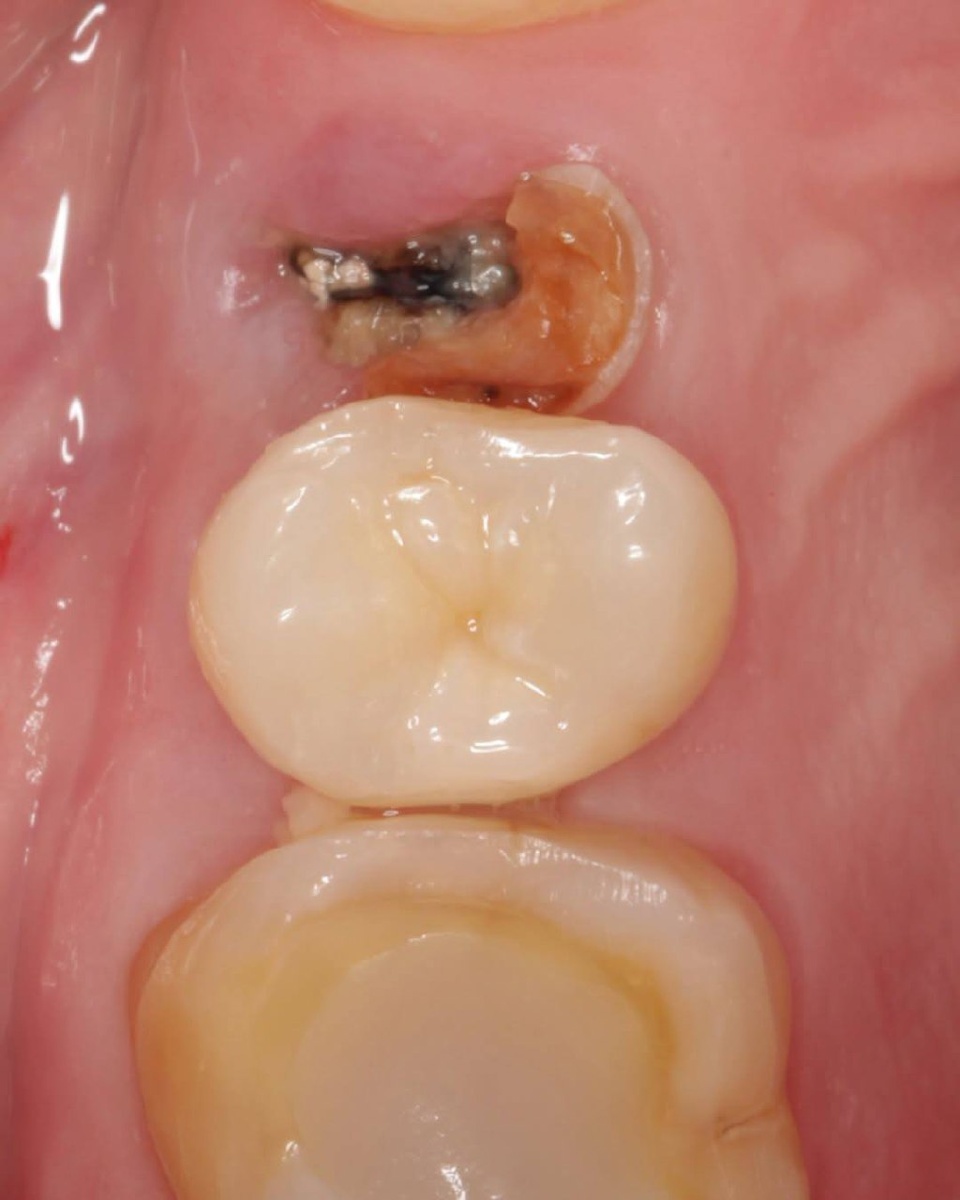

Клинический случай от Дмитрия Николаева @d_nicolaev До/После Работа выполнена за одно посещение: лечение пульпита с последующей прямой реставрацией. Препарирование каналов выполнено инструментами T flex (Eurofile). Основной канал отпрепарирован на всю длину до 35/02, второй - до точки схождения, ограничился 15/06. Для активации гипохлорита натрия использовал сочетание звукового активатора (Dialog) и ультразвука (Irri, Acteon). Обтурация - в гибридной технике с эпоксидным силером (АН plus). Прямая реставрация использовал адгезивную систему Prime&Bond Universal (DentsplySirona) в технике тотального травления. Композиты - Estelite bulk-fill (Tokuyama), NeoSpectra A3 (DentsplySirona), Asteria WE (Tokuyama). На контрольном снимке обратите внимание на низкую рентгеноконтрастность Estelite bulk-fill - из него выполнено ядро зуба, по неопытности можно ошибиться и принять его за очень неглубоко поставленный СВШ. После завершения работы, пациентка пересела в кресло хирурга для консультации и пла

До/После

Работа выполнена за одно посещение: лечение пульпита с последующей прямой реставрацией.

Препарирование каналов выполнено инструментами T flex

(Eurofile). Основной канал отпрепарирован на всю длину до 35/02, второй - до точки схождения, ограничился 15/06. Для активации гипохлорита натрия использовал сочетание звукового активатора (Dialog) и ультразвука (Irri, Acteon).

Обтурация - в гибридной технике с эпоксидным силером (АН

plus).

Прямая реставрация использовал адгезивную систему

Prime&Bond Universal (DentsplySirona) в технике тотального

травления. Композиты - Estelite bulk-fill (Tokuyama),

NeoSpectra A3 (DentsplySirona), Asteria WE (Tokuyama).

На контрольном снимке обратите внимание на низкую рентгеноконтрастность Estelite bulk-fill - из него выполнено ядро зуба, по неопытности можно ошибиться и принять его за очень неглубоко поставленный СВШ.

После завершения работы, пациентка пересела в кресло хирурга для консультации и планирования удаления зуба 24 с последующей имплантацией.